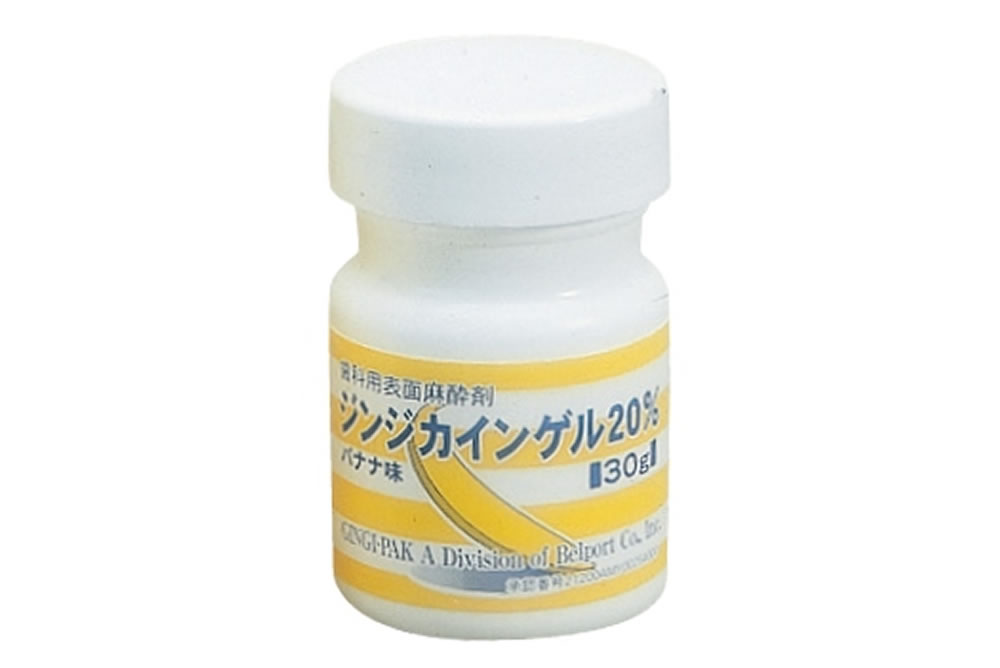

歯科治療における痛みや恐怖は、お子様が歯医者さんを嫌いになる大きな要因となります。当院では、痛みを伴う恐れがある処置には事前に麻酔注射を施し、痛みの緩和に努めています。

歯科治療における痛みや恐怖は、お子様が歯医者さんを嫌いになる大きな要因となります。当院では、痛みを伴う恐れがある処置には事前に麻酔注射を施し、痛みの緩和に努めています。

さらに、麻酔注射についても痛みをできるだけ感じないように様々な工夫を行っていますのでご安心下さい。